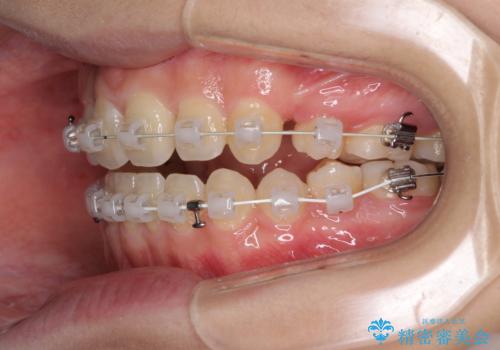

- 矯正装置

- 審美装置

- 3年3ヶ月

- 10-30回

上下前歯の前後位置が大きくずれていたため、上顎左右第一小臼歯2本を抜歯してワイヤー装置による矯正治療を行うこととしました。

オープンバイトの原因は舌の突出癖であり、癖が改善されないと治療経過に影響を及ぼすため、舌のトレーニングを指示しました。

なかなか癖が改善されず、トレーニングも断続的に行ったため、治療期間は長期化しました。